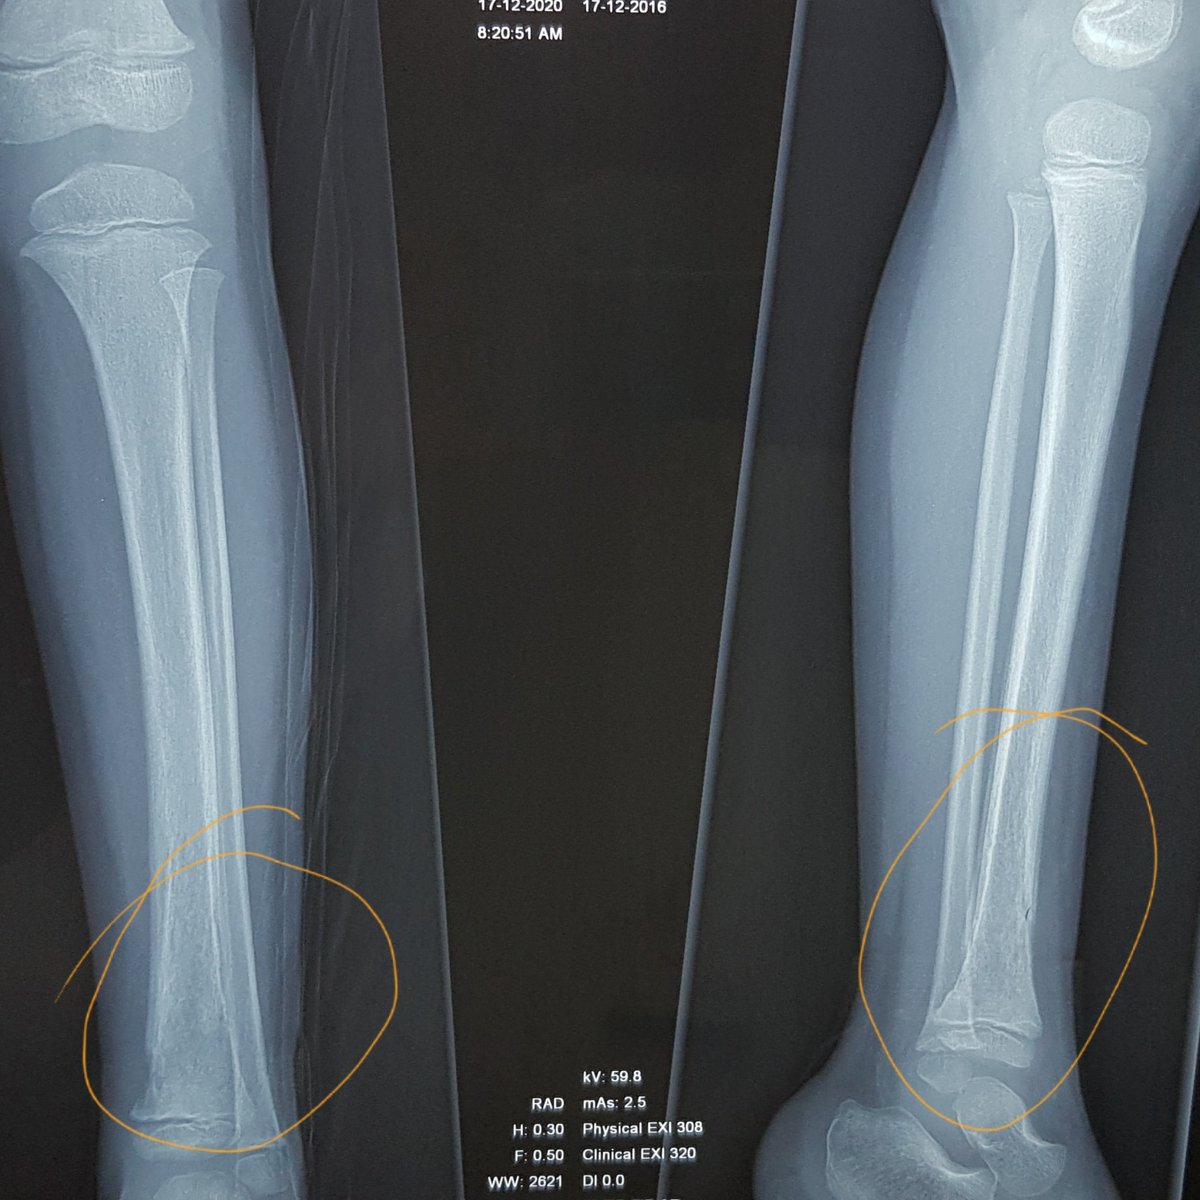

بعد ظهور الأشعة طبيعية -وتكون كذلك في الأيام الأولى- شخصناه بإلتهاب عظمة الساق،

(الأشعة المرفقة للساق بعد غياب اسبوعين، ونلاحظ تآكل طفيف في العظم في أسفل الساق)